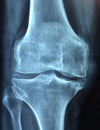

How to protect the cartilage of your joints from oxidative stress and degeneration.

source src=""https://tissuerecovery.com/wp-content/uploads/2018/11/untitled_x264.mp4"">   Oxidative stress tends to increase as we get older and contributes to cell death of cartilage. It also damages other tissue. This leads to increased cartilage degeneration, which can lead to arthritis, and you don’t want to get arthritis. In the following study, the researchers took...